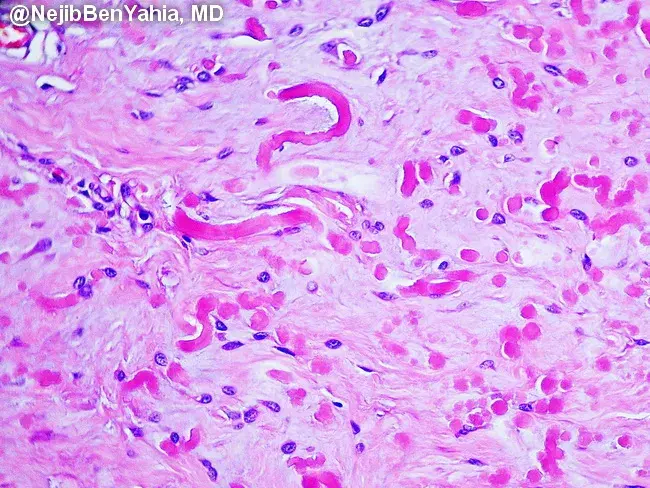

1)Fascéite nodulaire

2)

Moins de 3cm

3)

Accolé à un fascia (bande éosinophile) mais parfois dans le derme

Espaces myxoïdes et kystiques, parfois collagénique

Prolifération myofibroblastique : tissue culture avec aspect de tissu de granulation

Pas de pléomorphisme (parfois on retrouve des cellules ganglionaire like (photo)

Erythrocytes extravasés

Fibres musculaires disséquées

4)

SMA+, DES-,Caldesmon

5) MYH9-USP6